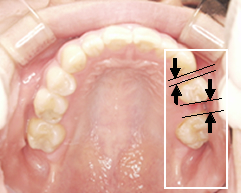

写真(1)

治療前

ブリッジ部分が虫歯になってしまった

ブリッジを外したところ

2ケ所にブリッジがあります